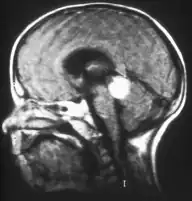

MRI pattern of retinoblastoma with optic nerve involvement (sagittal enhanced T1-weighted sequence)